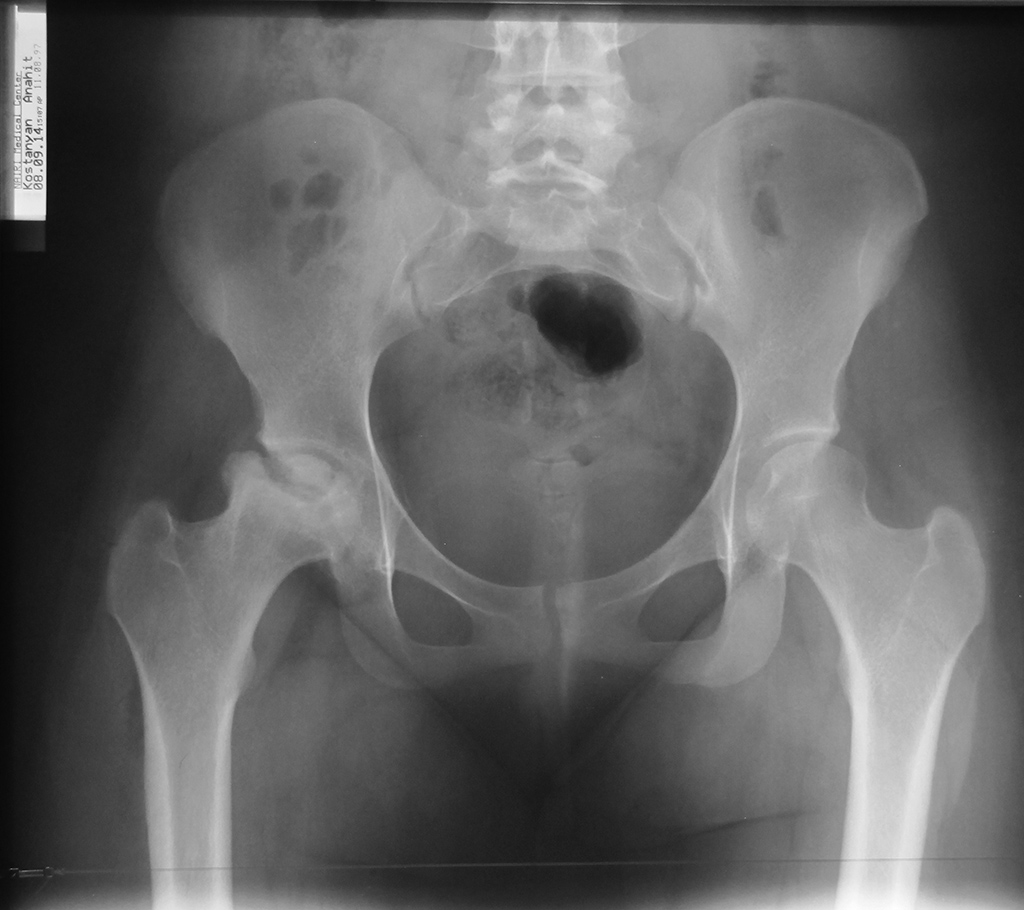

В пользу АНГБК говорят многие факторы: пол (нехарактерен для Пертеса, впрочем как и для и АНГБК), возраст, сопутствующая патология и т.п. Однако за болезнь Пертеса - течение процесса, завершившиеся фактически восстановлением формы головки и конгруэнтности суставной щели.

На рентгенограммах, вряд ли кто-то оспорит, динамика положительная. А как с клинической картиной? Если она тоже положительная, возможно не стоит спешить с эндопротезированием?

Ограничение отведения и частично боли могут быть обусловлены потерей офсета головочно-шеечного соединения и изменения его формы. При ремоделировании головки, восстановления ее сферичности и упомянутого офсета проблема ограничения отведения может быть решена. Сложно сказать по представленным рентгенограммам насколько ФАИ выражен в других отделах, но передний доступ и артроскопия ТБС едва ли восстановят в полной мере офсет верхнего и заднего отделов головки. Считаю, в данном случае оптимальней хирургический вывих.

Но настораживает выраженный остеопороз головки под нагрузочной зоной головки. После ремоделирования она может просто потерять латеральную опору, снова провалиться и о спасении головки и сустава можно забыть. Вот тогда придется точно заняться подбором эндопротеза.

> На рентгенограммах, вряд ли кто-то оспорит, динамика положительная. А как с клинической картиной? Если она тоже положительная, возможно не стоит спешить с эндопротезированием?

- насколько я понял из дат, "промятая" головка это уже в 14 году

Отправитель: Ильдар Ахтямов 27 Октябрь 2014, 11:35

Антон, боюсь, что твоя трактовка снимков ошибочна. Если взглянуть на даты рентгенограмм (13 и 14 год), то складывается картина развивающегося процесса. Произошла секвестрация. Это не Пертеса, а АНГБК. Наропинотерапия хороша до коллапса хрящевого слоя, но можно попробовать. В данном случае все средства хороши, однако боюсь, что все закончится тотальным протезированием с короткой ножкой и парой керамика-керамика. АИФ

Извините за ошибку, на устройстве фото снимков отобразилось в обратном хронологическом порядке. Конечно это АНГБК в предпоследней стадии. Речи о сохранении головки уже не идет.((((

No, it;s been deteriorating! (2013 - 2014).